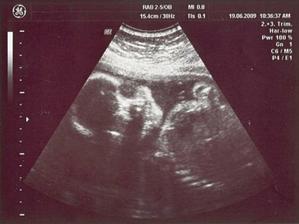

26/3 09 PORADNA 14 + 4 tt - přítel nesmí chybět, žížalka povyrostla, je to mrška neposedná, ani chvíli není v klidu, dr. má problémy vystihnout okamžik aby byla fotka z utz pěkná, nakonec máme fotečky dvě, na jedné jdou vidět oči - vypadá jak marťan 🙂), dr. slíbila že na příští KO už budeme vědět pohlaví ... čekání do 28/4 bude nekonečný